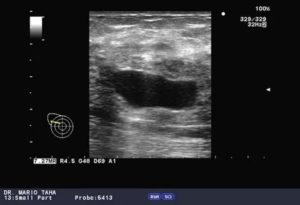

Как выглядит киста яичника на УЗИ

Основной признак кисты яичника на УЗИ – формирование на его теле полого отростка. Он отличается от нормального фолликула тем, что, на протяжении цикла, никак не меняется. К тому же, такое новообразование имеет больший размер.

На снимке УЗИ, киста яичника выглядит черным пятном, размером от 3 до 20 см.

Геморрагическая

Такое образование представляет собой кровяной сгусток. Его структура – однокамерная, гипоэхогенная. Включения могут быть разными, например, с нитями фибрина.

Толщина стенки такого новообразования – вариабельная. Часто она имеет кровеносные сосуды, расположенные циркулярно.